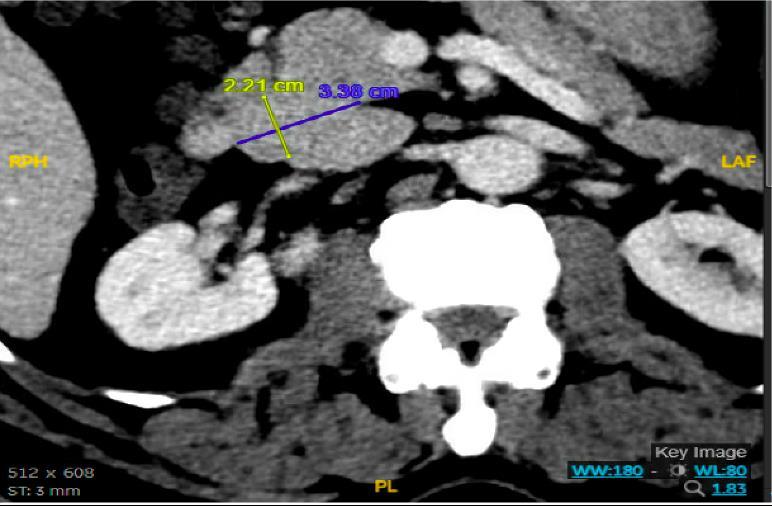

CASE PRESENTATION: A 67-year-old male with a history of partial liver resection, peptic ulcer disease, and Helicobacter pylori gastritis s/p quadruple therapy presented with acute on chronic abdominal pain despite being on a proton pump inhibitor (PPI). He had abdominal pain for the past 5 years associated with nausea, vomiting, diarrhea, and a 50-pound unintentional weight loss. An esophagogastroduodenoscopy (EGD) six months ago demonstrated peptic ulcer disease and Helicobacter pylori which was successfully eradicated.

He underwent a CT-abdomen/pelvis with intravenous contrast in the emergency department which revealed an enhancing 3.4 cm mass in the head of the pancreas with retroperitoneal lymphadenopathy. MRI of the abdomen confirmed the presence of a 3.2 cm enhancing pancreatic head mass with direct extension into the second portion of the duodenum and multiple enlarged retroperitoneal lymph nodes. EGD was remarkable for edema and granularity in the first portion of the duodenum. Endoscopic ultrasound (EUS) was notable for a hypoechoic and heterogeneous irregular mass in the pancreatic head measuring 25 mm by 23 mm in maximal crosssectional diameter with invasion into the serosa and muscularis mucosa of the duodenum. Fine needle aspiration of the pancreatic mass for cytology revealed a well-differentiated pancreatic neuroendocrine tumor (Ki-67 index <1%). Gastrin levels were ordered. He presented again to the hospital 3 weeks later with worsening epigastric abdominal pain and nausea despite adhering to PPI therapy. CT-abdomen revealed new proximal duodenal ulcerations. Gastrin level from the prior admission was noted to be 1988 pg/mL. He subsequently underwent a Whipple's procedure with no complications and was discharged home with a planned EGD surveillance in 6 months.

CONCLUSION: Establishing a diagnosis of ZE can be difficult due to the lack of consistent diagnostic criteria, the widespread use of PPIs that masks mask the symptoms and limited access to gastric pH testing. In our case, the diagnosis was based on a fasting serum gastrin level, FNA results, and imaging findings. Owing to its variable clinical presentation, high mortality, and challenging primary lesion identification, clinicians should consider ZE in the differential diagnosis of patients who are symptomatic despite taking PPI, having Helicobacter pylori successfully eradicated or having multiple duodenal and gastric ulcers that fail to respond to therapy.

Figure 1: CT Abdomen and Pelvis with contrast showing a suspicious mass in the second portion of the duodenum/pancreatic head.